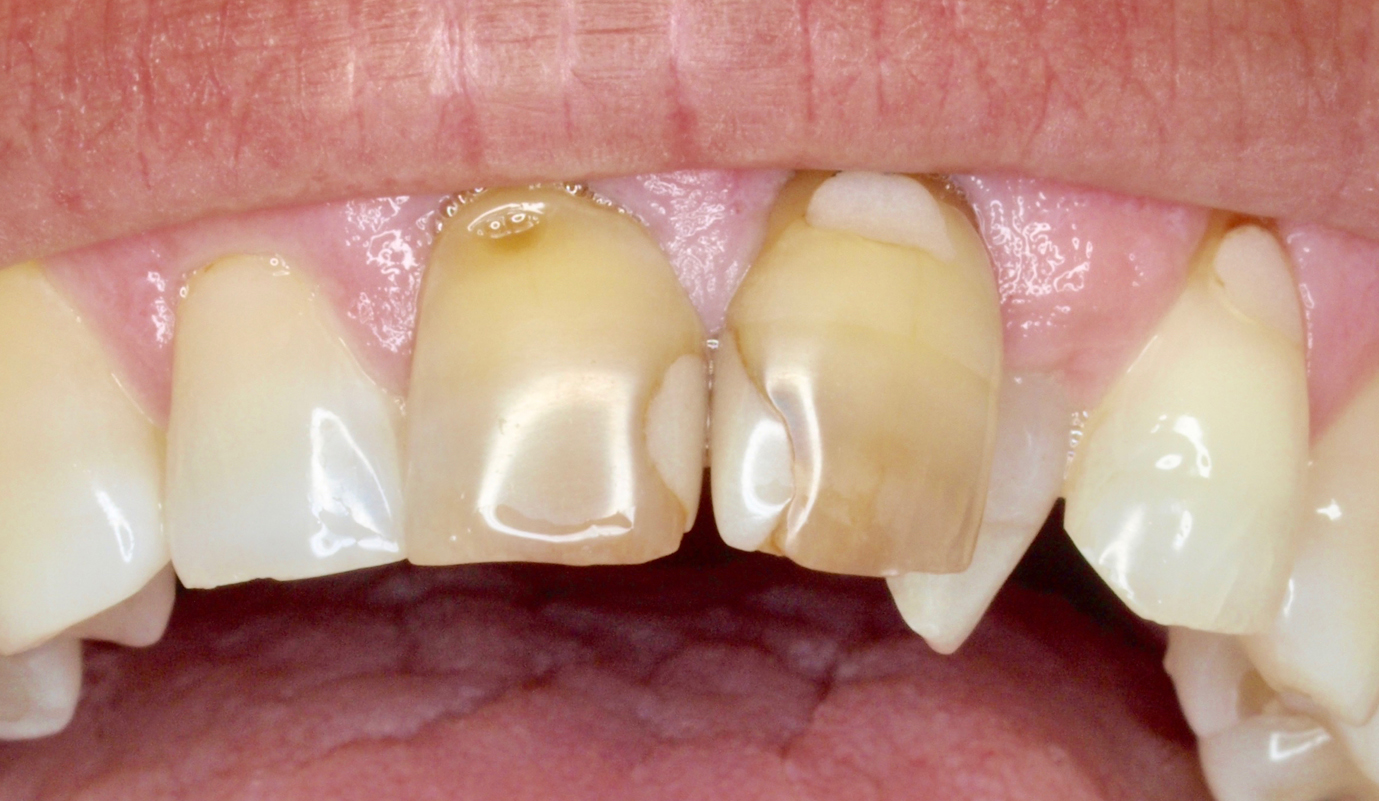

- Melhorar a aparência dos dentes quebrados ou danificados por cáries;

Casos de prótese fixa sobre dentes